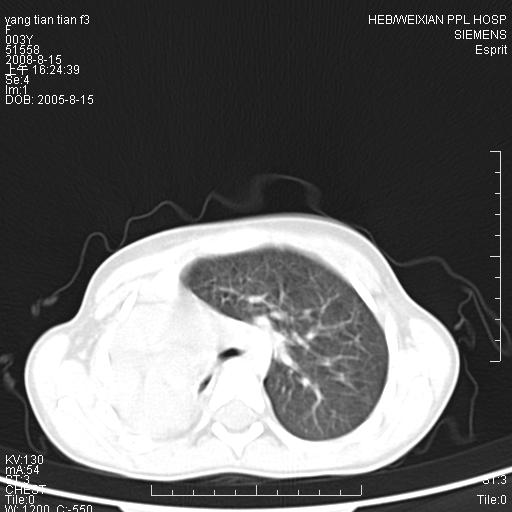

患儿,女,5岁,平素活动后气短,左侧面瘫.右侧胸廓较左侧塌陷.

两侧胸廓不甚对称,左侧稍膨隆,右肺体积明显变小,密度增高,未见正常通气肺组织,纵隔结构明显右移,心脏边缘欠清,外形似增大。纵隔血管间隙不清晰,左肺外形增大,部分肺组织突向右侧胸腔,左肺内未见异常密度影,右侧支气管逐渐变细,其内未见异常密度影。右侧未见叶及段支气管。右侧膈肌升高。

1。右肺体积小(考虑右肺发育不全)

2。左肺代偿性增大

3。心影增大?